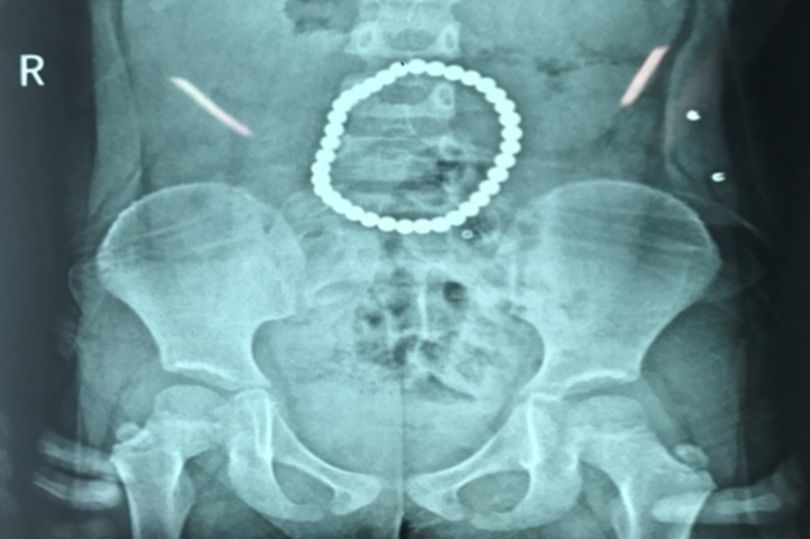

Nuốt hàng chục bi nam châm, bé 3 tuổi thủng dạ dày lỗ chỗ

Một bé gái ba tuổi đã phải đi bệnh viện cấp cứu vì đã nuốt vào bụng một chuỗi các hạt nam châm chọc thủng dạ dày cô bé.